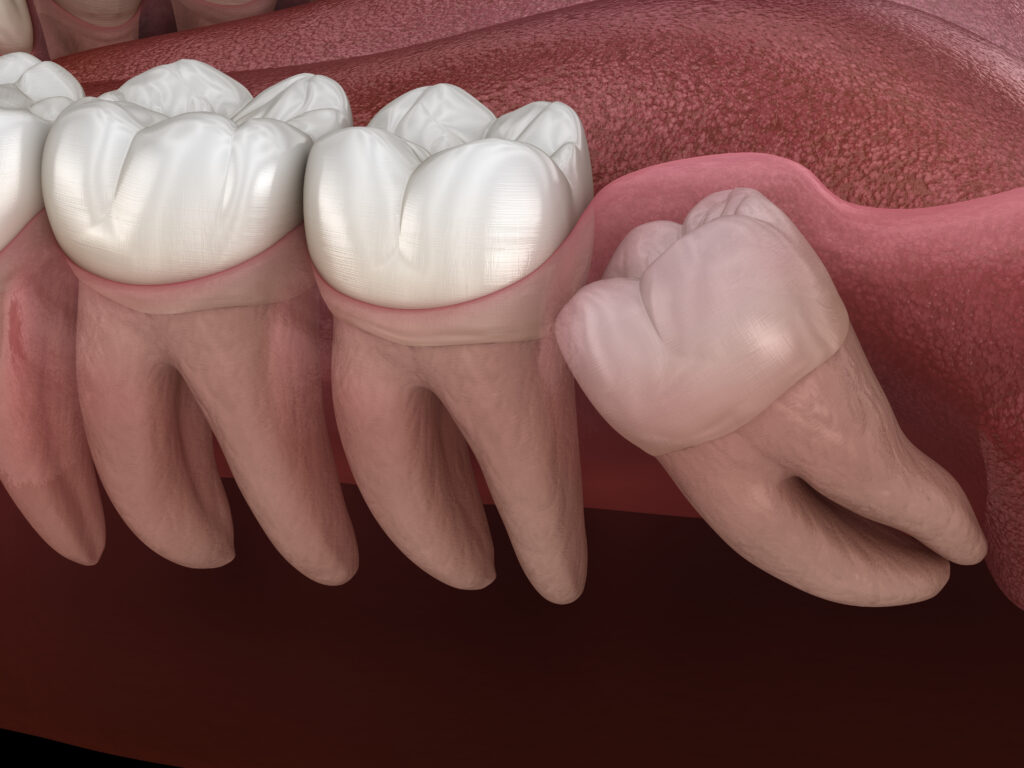

Removal of a Retained Wisdom Tooth

A retained wisdom tooth (also called an “impacted tooth”) is one that remains partially or fully trapped in the gum…

• The need for tooth extraction due to severe tooth destruction, chronic infection (dental abscess surgery), or a troublesome, partially erupted wisdom tooth.

Do Wisdom teeth always need to be removed – Debunking Common Myths

Wisdom teeth are the teeth that most often cause unexpected issues. Some people live with them comfortably throughout their lives, while for others, they develop into impacted teeth, causing complications. Wisdom teeth behave differently, and there’s no single answer — to remove or not to remove. A personalized approach is essential to determine whether wisdom […]